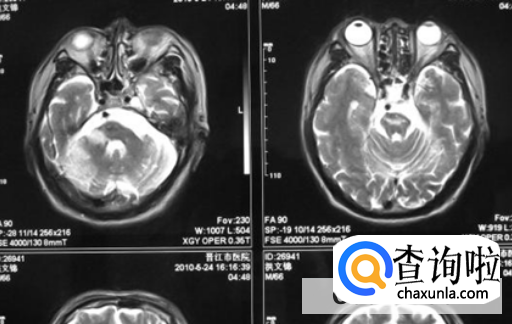

总是感觉头发晕眼花,而且一点精神没有抬头的时候也特别的费力,其实有可能会是脑梗塞的前兆,在这个时候可以通过拍CT的方式看一下,那内部的情况CT能够看到是否有堵塞的现象,如果出现脑梗塞还是在早期及时的进行治疗。